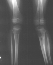

At this time the child was experiencing significant pain and inability to ambulate. He was treated with varus producing closing wedge osteotomy of the proximal tibia with neutral alignment

X-Ray Set 3. Post-Op, Neutral alignment

X-Ray Set 4. 3 Months post Surgery , Left 6* Mechanical axis

X-Ray Set 5. 9 Months post Surgery Left 10* Mechanical axis